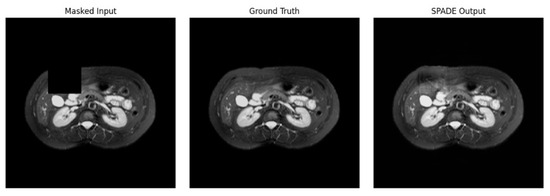

The rapid development of Generative Adversarial Networks (GANs) has transformed medical image processing, enabling realistic image synthesis, augmentation, and restoration. This study presents a comparative evaluation of three representative GAN architectures, Pix2Pix, SPADE GAN, and Wasserstein GAN (WGAN), across multiple medical imaging tasks,

The rapid development of Generative Adversarial Networks (GANs) has transformed medical image processing, enabling realistic image synthesis, augmentation, and restoration. This study presents a comparative evaluation of three representative GAN architectures, Pix2Pix, SPADE GAN, and Wasserstein GAN (WGAN), across multiple medical imaging tasks, including segmentation, image synthesis, and enhancement. Experiments were conducted on three benchmark datasets: ACDC (cardiac MRI), Brain Tumor MRI, and CHAOS (abdominal MRI). Model performance was assessed using Fréchet Inception Distance (FID), Peak Signal-to-Noise Ratio (PSNR), Structural Similarity Index (SSIM), Dice coefficient, and segmentation accuracy. Results show that SPADE-inpainting achieved the best image fidelity (PSNR ≈ 36 dB, SSIM > 0.97, Dice ≈ 0.94, FID < 0.01), while Pix2Pix delivered the highest segmentation accuracy (Dice ≈ 0.90 on ACDC). WGAN provided stable enhancement and strong visual sharpness on smaller datasets such as Brain Tumor MRI. The findings confirm that no single GAN architecture universally excels across all tasks; performance depends on data complexity and task objectives. Overall, GANs demonstrate strong potential for medical image augmentation and synthesis, though their clinical utility remains dependent on anatomical fidelity and dataset diversity.